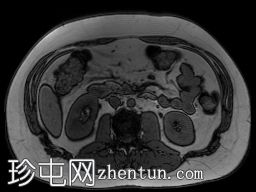

轴位

T2加权像

T1低信号,T2低信号为主的脾脏肿块,内部可见T2高信号分隔,呈进行性强化。肿块中央可见星状瘢痕。

脾脏硬化性血管瘤样结节性转化(SANT),9.8 cm肿块

顾名思义,脾脏硬化性血管瘤样结节性转化(SANT)是一种纤维性血管病变。本病例展示了SANT的一些典型影像学特征,包括边界清晰的病灶,中央可见瘢痕,以及呈放射状进行性强化。这些特征使得术前MRI诊断较为明确。尽管SANT是一种良性病变,但大多数患者仍需行脾切除术以明确病理诊断。